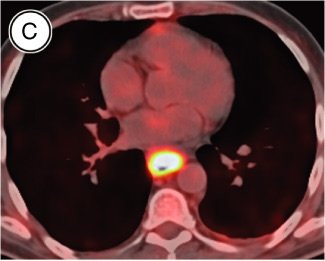

TOMOGRAFIA POR EMISSÃO DE PÓSITRONS (PET)

O papel da PET no estadiamento do câncer de esôfago continua sendo um tópico discutido.

18 - Fluorodesoxiglicose FDG PET aumenta a identificação de metástases a distância, com aumento na emissão das áreas com metabolismo da glicose aumentado (incluindo câncer), mas com poucos detalhes anatómicos.

A principal característica da PET é não depender de distorção arquitetural ou anatómica para detectar malignidade. A PET produz imagens do corpo todo em três dimensões, mas sem resolução anatómica para avaliar disseminação metastática e doença primária. Enquanto a sensibilidade e a especificidade são comparáveis ou excedem a TC, ambas são pobres para o estadiamento definitivo.

A desvantagem da PET consiste na captação intracelular de FDG não ser específica para tumores, além do fato de as áreas de inflamação também predisporem a resultados falsos-positivos. Uma vez que a PET é uma técnica de emissão baseada no aumento do metabolismo celular, e não em alterações anatómicas, o nível de invasão tumoral (estádio T) não pode ser determinado e os linfonodos peresofágicos diretamente adjacentes ao tumor dificilmente são distinguíveis do tumor primário.

Apesar de a PET ser mais confiável que a TC, isoladamente, para a identificação de doença metastática, as vantagens funcionais da PET podem ser combinadas com a superioridade anatómica da TC para aumentar a taxa de detecção de metástases para 80% a 90% de acurácia.